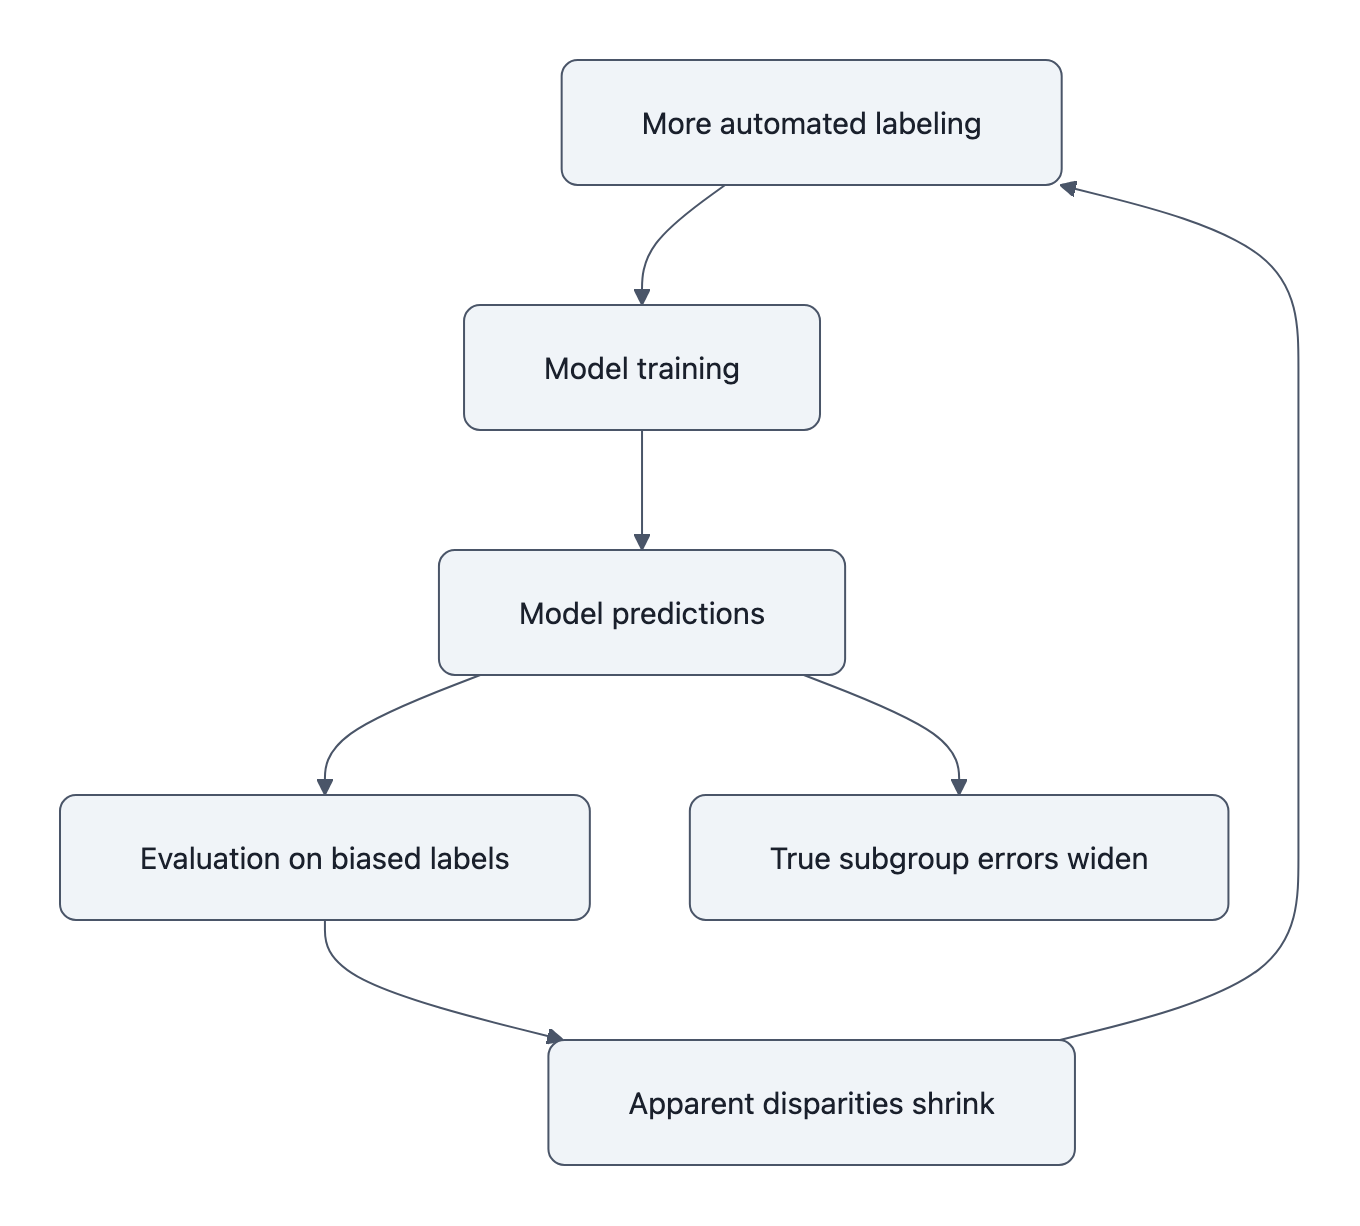

Automation can amplify bias: what the MAMA‑MIA audit shows

Here’s where the story gets stranger.

You might think: “Okay, the labels are biased. But at worst, models will inherit that bias, not go beyond it.”

The MAMA‑MIA audit finds something nastier: when you train segmentation models directly on the biased automated labels, age disparities grow, by on the order of 40% in their experiments, compared to training on cleaner human annotations.

The pipeline looks innocent:

- Use a strong model (or ensemble) to auto‑segment tumors in a large dataset.

- Treat those as “ground truth” labels, maybe with cursory checks.

- Train a new model on this big, shiny dataset.

- Evaluate it on a test set that is labeled… in exactly the same way.

What can go wrong?

Under the hood, automated labels tend to be most accurate on the majority, “easy” subgroup, the older patients with textbook tumor morphology. They’re least reliable on the atypical, harder distributions, the younger patients with weird, jagged lesions.

So the new model gets:

- Extremely consistent training signal on older cases (lots of similar shapes, all reinforced).

- Inconsistent, sometimes outright wrong signals on younger cases (shapes that don’t fit the learned template, labels that occasionally lie).

Standard optimization does the obvious thing: it fits the clean, abundant pattern and treats everything else as noise. That’s how bias amplifies.

Then the biased ruler comes back. You evaluate the biased model on a biased test set:

- It agrees beautifully with the automated labels on older patients, high scores!

- It agrees more often with the labels’ errors on younger patients, still decent scores!

The benchmark reports narrow gaps or none at all. Underneath, the model’s actual performance divergence has widened.